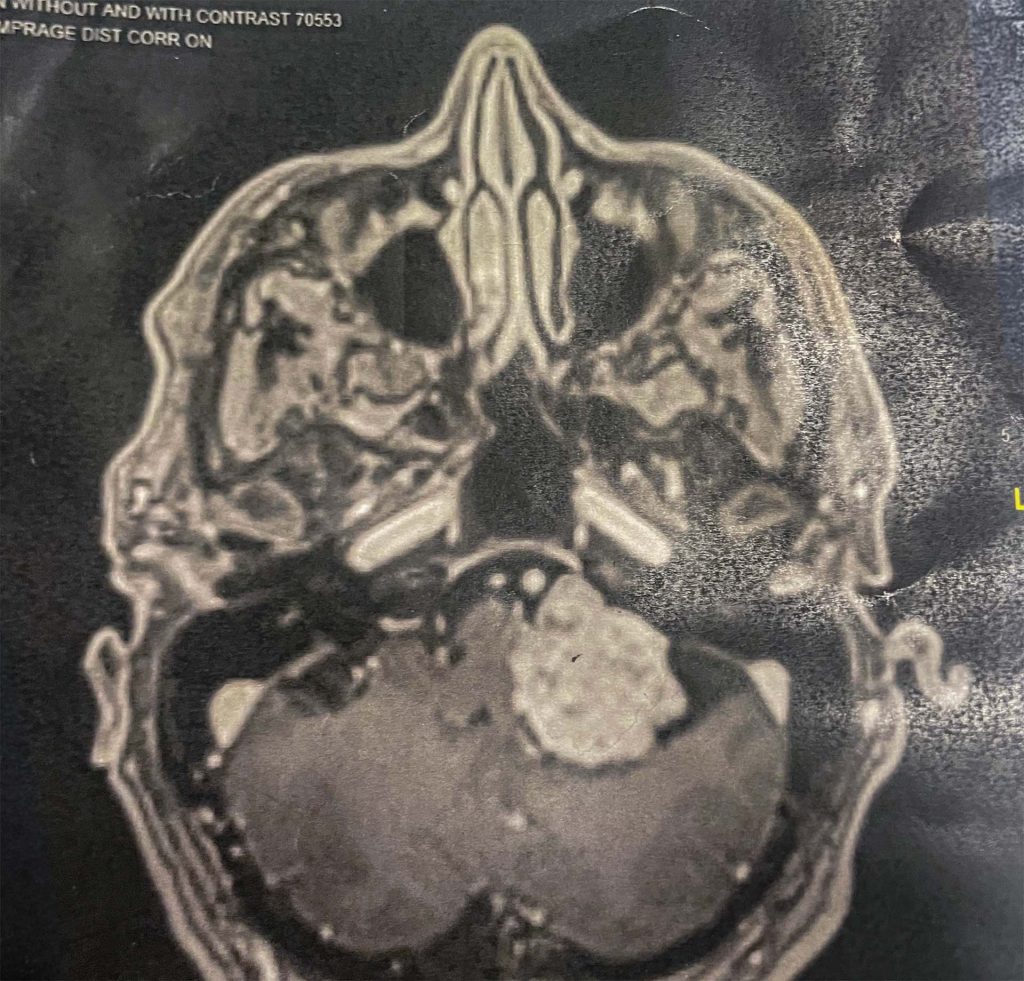

When Kevin arrived at the emergency department at Inspira Health Mullica Hill, his fears were confirmed. After a series of tests, including a CT scan, a diagnosis was confirmed: a rare 4 cm hypoglossal schwannoma tumor.

“I had a major brain tumor. At that point, I thought, ‘This is it,’” Kevin said. The team at Inspira urged him to see a neuro specialist immediately who could review the results and outline next steps. They recommended arranging for a transport to Cooper University Hospital that night.

When arriving at Cooper by ambulance, Kevin was quickly met by Saniya Godil, M.D. Upon reviewing the films and results from Inspira, she recommended immediate tumor resection surgery to remove the brain tumor. Kevin was hesitant. He didn’t want to believe his condition was that serious.

The brain tumor procedure was a major success, though it turned out to be more complex than anticipated.

“This was a large tumor that was in a very critical area of the brain. It’s one of the most challenging types of tumors in our specialty.”

What was expected to be a 4 to 6 hour operation stretched into 18 hours.